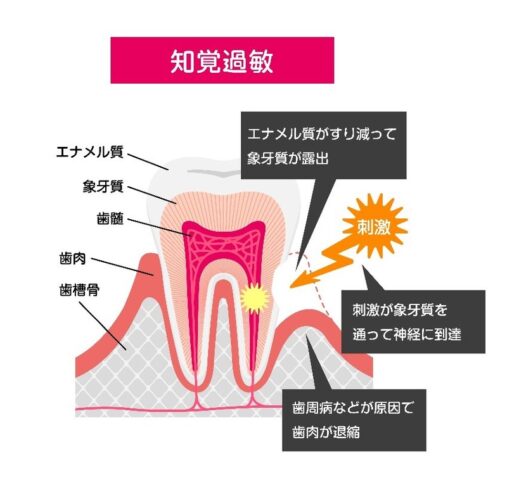

知覚過敏はなぜ起こる?

原因と予防法を歯科衛生士がわかりやすく解説歯が「キーン」としみるのは知覚過敏かも?冷たい飲み物を飲んだときや、歯みがきをしたときに「キーン」と鋭い痛みを感じたことはありませんか?それは、知覚過敏の症状かもしれません。知覚過敏は、誰にでも起こ...